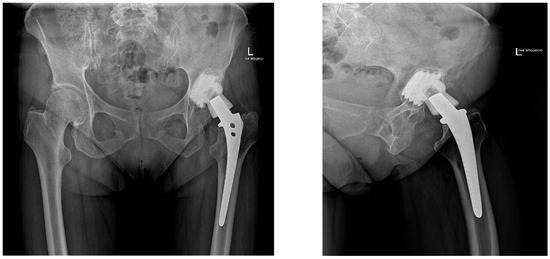

Minimum Two-Year Outcomes of the Zimmer G7 Modular Dual Mobility Cup in Primary Total Hip Arthroplasty: Survivorship, Complications, Clinical and Radiographic Results

Background/Objectives: Modular dual mobility (MDM) cups are constituted by a cobalt-chromium liner inserted into a standard acetabular shell, allowing for intraoperative indication and supplementary screw fixation of the acetabular component. MDM could face mechanical and biological issues, with the associated risk of elevated [...] Read more.

Background/Objectives: Modular dual mobility (MDM) cups are constituted by a cobalt-chromium liner inserted into a standard acetabular shell, allowing for intraoperative indication and supplementary screw fixation of the acetabular component. MDM could face mechanical and biological issues, with the associated risk of elevated blood metal ions levels and adverse local tissue reactions. Methods: This is a monocentric retrospective study on a consecutive series of 105 patients who underwent primary unilateral THA with the G7 Dual Mobility Acetabular System cup (Zimmer Biomet, Warsaw, IN, USA) from March 2019 to April 2023, and who were evaluated clinically and radiographically at a minimum two-year follow-up. All complications and revisions were recorded. Survivorship analysis with any revision surgery as endpoint was performed using Kaplan–Meier survival curves. Results: There were eighty-nine patients (follow-up rate 84.8%) who underwent clinical and radiographic follow-up. The mean follow-up was 2.5 ± 0.8 years. Revision-free survival was 98.0%. Three complications (2.8%) were recorded: one case of posterior dislocation, one periprosthetic joint infection and one post-traumatic periprosthetic femur fracture. Dislocation rate and infection rate were less than 1.0%. None of the patients were revised for adverse local tissue reactions. No cup loosening was observed. No cases of intraprosthetic dislocation, liner malseating or femoral notching were observed. Retroacetabular stress shielding was present in 43.0% of patients. Clinical scores significantly improved at the last follow-up compared with preoperative status (p < 0.0001): the final mean mHHS was 87.5 ± 5.3 and the final mean VAS was 0.5 ± 0.9. Conclusions: The Zimmer G7 modular dual mobility cup appears to be a safe and effective option and does not present specific implant-related mechanical and biological issues in primary total hip arthroplasty at a minimum two-year follow-up. Full article